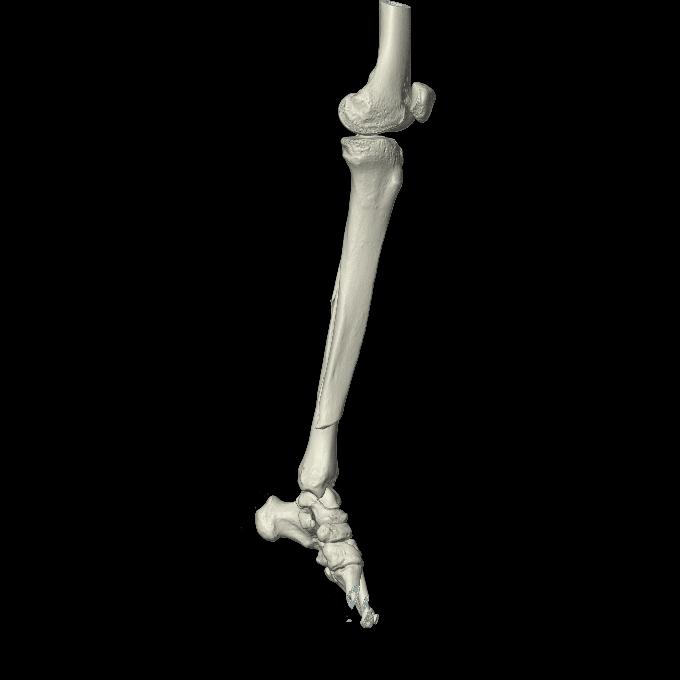

102803 1/12(キウスなし) 1/27 左下腿 4R 30歳女性 左脛骨軸内釘